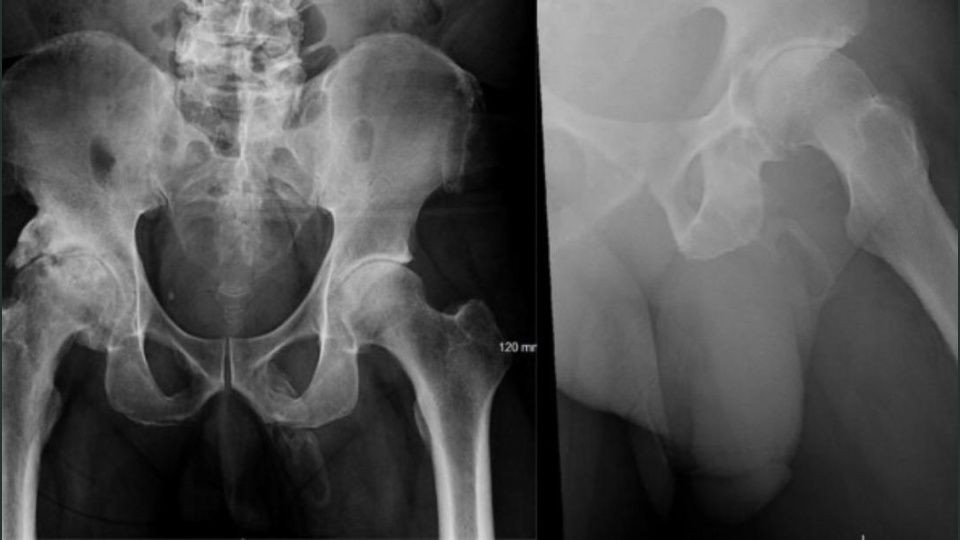

Al realizarle una radiografía para verificar que no se había roto la cadera mostró tejido óseo formándose en su pene.

Un extraño caso médico fue informado en Estados Unidos. Se trata de un hombre que descubrió que su pene se está volviendo hueso cuando los médicos le toman radiografías de las caderas después de una caída. El paciente fue visto por médicos en el Bronx, Nueva York, después de caer en la calle.

Mientras lo revisaban, los médicos le tomaron una radiografía de la pelvis para verificar que no había huesos rotos, pero encontraron algo más extraño de lo que esperaban.

Lo diagnosticaron con una osificación, lo que significa que una parte del cuerpo se convierte lentamente en hueso.

En un informe de caso, los médicos, dirigidos por Georges El Hasbani de la Universidad Americana de Beirut, dijeron que la afección es "extremadamente rara". La osificación del pene sigue siendo una condición relativamente rara que se menciona en muy pocas revistas, con menos de 40 informes de casos publicados